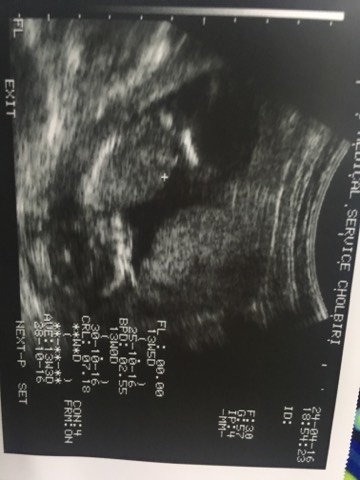

อายุครรภ์กี่สัปดาห์ถึงเห็นเพศลูกคะ

รบกวนหน่อยค่ะ ตอนนี้ตัวดิฉัน อายุครรภ์ได้ 16 สัปดาห์ 2 วัน สามารถซาวน์เห็นเพศลูกได้หรือยังคะ

ครั้งที่แล้วซาวน์ตอน12 สัปดาห์ยังไม่เห็นเพศน้องเลยค่ะ